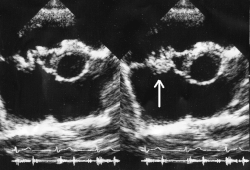

Вегетации на трикуспидальном клапане, видимые при эхокардиографии. Стрелкой указана вегетация.

Окончательный диагноз устанавливают при получении положительных результатов посева крови и данных об обнаружении вегетаций при эхокардиографии.